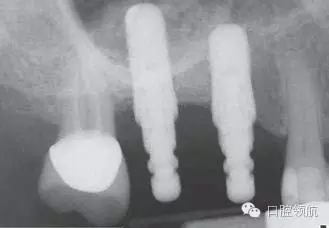

8個(gè)月后,植入2顆種植體,并獲得了良好的初期穩(wěn)定性(圖10)。雖然計(jì)劃上頜竇底提升同期植入種植體,但如果出現(xiàn)上頜竇黏膜穿孔時(shí),不建議同期植入種植體。

圖10 術(shù)后8個(gè)月植入種植體時(shí)的X線片。